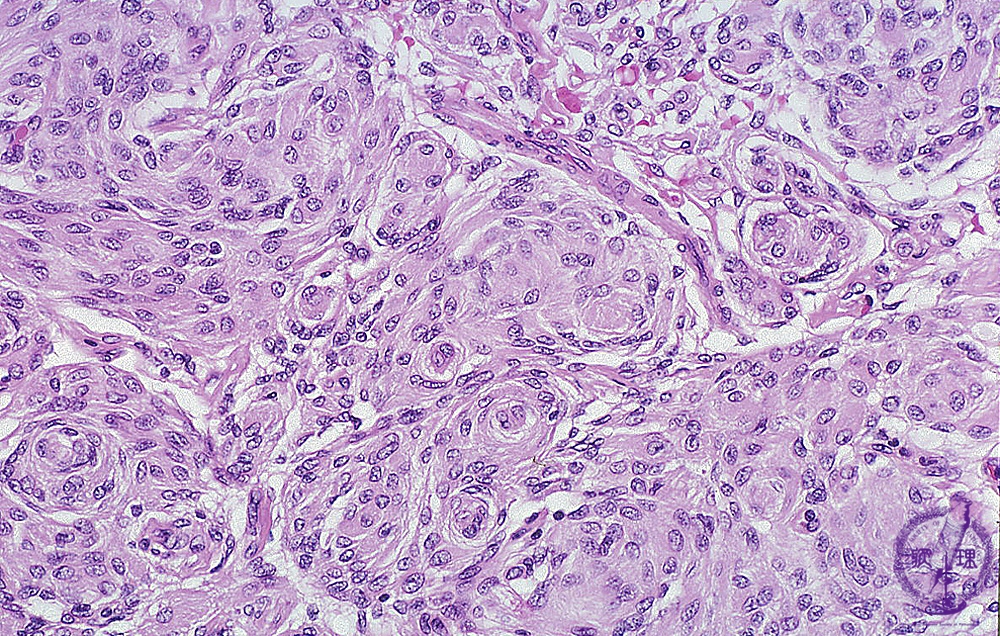

Microscopic findings (H.E. high magnification): Meningothelial meningioma showed a proliferation of tumor cells with round nuclei and unclear cellular junctions. Whorl formation of the tumor cells was seen in a scattered pattern within the tumor nests.